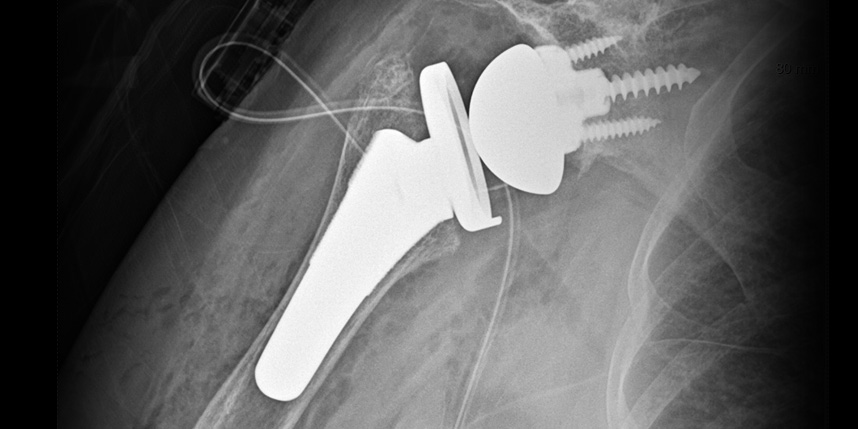

삼하게 망가져 거의 기능이 없는 관절을 제거한 후 특수하게 제작된 인공관절을 삽입하는 수술

역행성 인공관절 전치환술

역행성 인공관절 진치환술

(회전근개 심한 파열 및 관절염 진행)